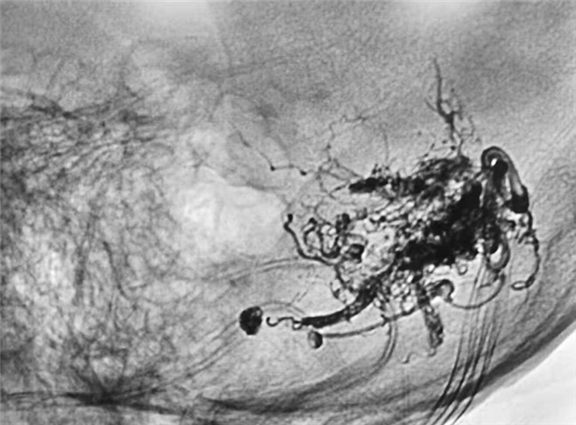

用微弹簧圈栓塞颅内动脉瘤,用ONXY胶栓塞血管畸形团,注胶过程中可以充分显示畸形血管,准确判断胶的走行,有利于保护周围正常血管,有效减少过度栓塞导致脑梗死等并发症

栓塞术后造影动脉瘤致密栓塞,小脑畸形血管团消失,术后患者恢复良好